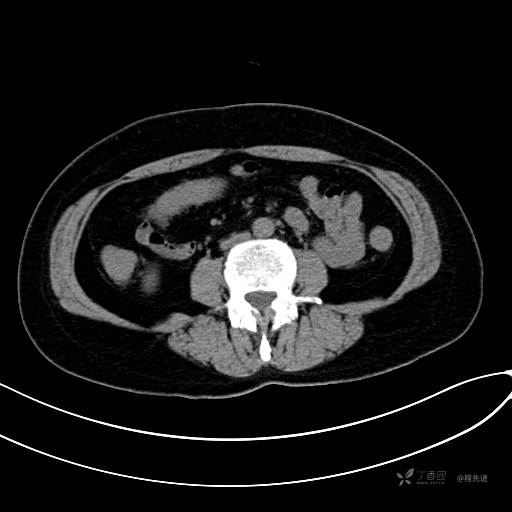

CT平扫